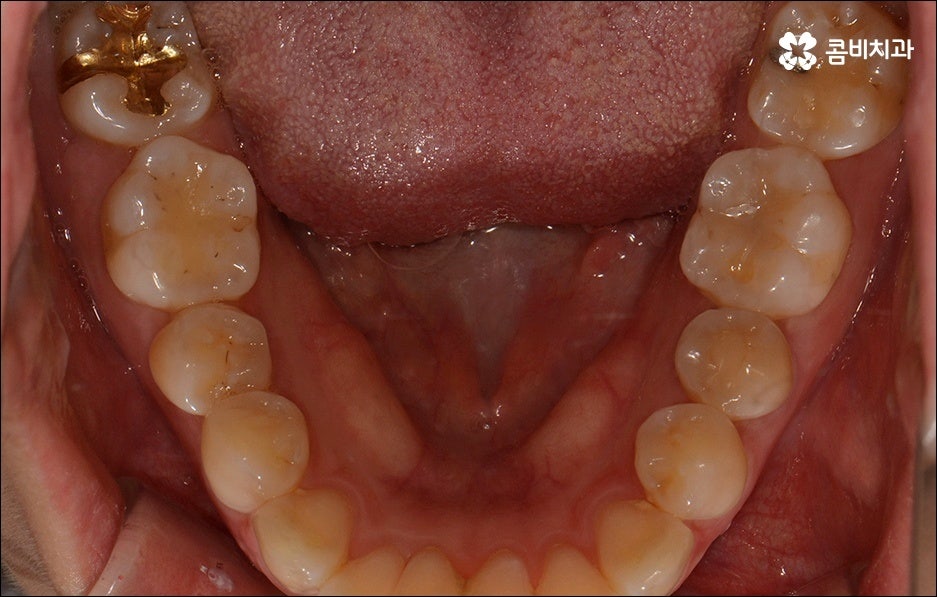

치열이 불규칙하여 기능적 심미적인 불편을 겪는 분들 중에 교정 치료를 고민하시는 분들이 많이 있습니다. 특히 앞니는 다른 치아보다 훨씬 외부에 잘 드러나므로 대화하거나 웃을 때 만약 앞니 사이가 벌어져 있거나 앞니 돌출 이 된 경우, 비틀어진 경우에는 신경이 많이 쓰일 수 있는데요. 하지만 막상 교정을 시작 하려고 하면 기간이 오래 걸리는 것 때문에 또는 치료 과정 자체에 부담을 느껴서 망설이시는 분들도 있을 수 있어요. 이때 앞니 외 다른 치아 배열 또는 위아래 교합에는 별다른 이상이 없다면 문제가 있는 앞니만 부분교정으로 치료할 수 있으니 이에 대해서 한 번 알아보시면 도움이 되실 거예요.

앞니가 튀어나오는 원인은 무엇일까요? 앞니 돌출 의 원인은 치아 크기가 큰 데 반해서 골격이 많이 작거나 상하악골 크기 차이가 많이 나는 것처럼 유전적인 요소에 기인하는 경우가 많으나 후천적인 생활 습관으로 인해서 발생하고 강화될 수도 있기 때문에 주의하실 필요가 있어요. 예를 들어 어릴 때 부터 손톱을 물어뜯거나 손가락을 자주 빠는 습관, 혀로 앞니를 밀면서 빼물곤 하는 습관을 가지고 있었다면 이로 인해 앞니가 튀어나올 수도 있는 거예요. 또한 축농증, 비염 등의 질환으로 인해 구호흡을 하게 되었다면 이것이 원인으로 작용할 수도 있으니 필요하다면 이비인후과와 협진을 하는 등 원인파악과 개선을 전반적으로 함께하시길 권유드리고 있어요.

하지만 보통은 돌출된 앞니 뿐 만 아니라 골격적인 부분이 원인이 되는 경우가 많으며 이런 경우에는 상태에 맞게 전체적으로 교정을 진행하여야 교합이 올바르게 되고 입매가 전체적으로 균형감 있게 개선될 수 있어요. 이런 경우에 골격적인 원인을 무시한 채 무리하게 치아의 각도만 안쪽으로 넣으려고 하면 자칫 옥니가 될 수도 있기 때문에 이러한 부작용을 막기 위해서도 환자분들의 상황을 정확하게 검진하고 그에 맞는 교정 플랜을 세우는 것이 필요한 거예요. 물론 부정교합 정도가 심각하고 골격적인 원인이 이미 굳어진 경우와 같이 수술이 함께 필요한 케이스도 있을 수 있으나 교정 치료만으로도 튀어나온 앞니가 들어가면서 자연스럽고 부드러운 인상으로 바뀌는 경우도 많으니 먼저 검진과 상담부터 꼼꼼하게 진행해 보시길 권유드리고 있습니다. 특히 개개인의 치열, 교합, 잇몸 상태, 구강구조 등을 면밀하게 파악하고 그에 따른 정확한 치료 계획을 수립할 수 있는 경험 많은 의료진과 함께 하는 것이 중요할 수 있어요.

골격적인 부분이 원인이 되는 경우 치료 시기 역시 중요할 수 있는데요. 성장기가 끝나고 잇몸뼈가 굳어지기 전에 상악과 하악의 균형잡힌 발달을 유도하는 것이 필요하기 때문에 윗턱에 비해 아래턱이 많이 작다면 2차 성징이 나타나기 전에 치료를 시작하는 것이 좋을 거예요. 2차 성장 시기는 성별 (여자 아이가 남자 아이보다 빠름) 및 개인마다 차이가 나지만 보통 10~12세 사이이니 필요하다면 이때 아이와 함께 치과에 내원하시길 추천드리고 있는데요. 돌출입 구조에 있어서 유전의 영향은 30% 정도이니 만약에 부모님께서 상악골이 돌출된 부정교합을 가지고 있다면 더욱 관심을 가지고 아이의 치열을 관찰하셔서 치료 시기를 조율해 보시는 게 좋을 거예요. 또한 상황에 따라 교정 치료 전에 충치나 잇몸을 먼저 치료하는 과정이 필요할 수 있으니 시작 시기나 전체 기간, 방법 등 자세한 사항들에 대해서 면밀한 검진 후 충분하게 상담부터 받아 보시길 권유드리고 있습니다.